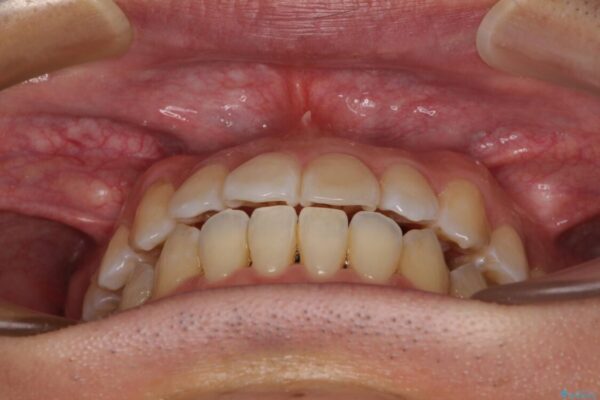

治療前

• 左右の八重歯が気になる ワイヤー装置での咬み合わせ改善 治療前画像